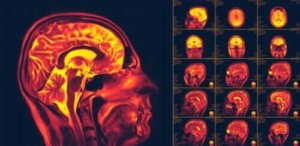

Aivojen neuroplastisuus, tai aivojen muovautuvuus, on yksi merkittävimmistä viimeaikaisista löydöistä ihmiskehossa. Se on aivojen kykyä muokata itseään ja sopeutua uusiin käyttäytymismalleihin tai kokemuksiin.

Sitten tutkijat kuitenkin havaitsivat, että aivojemme hermosolut voivat uudistua jatkuvasti. Ne tekevät tämän anatomisesti, mutta lisäksi ne voivat muodostaa uusiakin yhteyksiä. Tämä on se käsite, joka tunnetaan yleisesti nimellä “aivojen neuroplastisuus”. Se saattaa kuulostaa yksinkertaiselta, mutta todellisuudessa se on melko ihmeellinen kyky: neuroplastisuuden ansiosta aivot voivat jopa toipua tietyistä vammoista tai häiriöistä.

Tutkijat alkoivat kiinnittää tähän huomiota 1960-luvulla. He tutkivat erityisesti lukuisia aivoinfarktitapauksia aikuisten potilaiden kohdalla, ja yllättäen huomasivat, että monet näyttivätkin toipuvan vamman jälkeen. Tämän jälkeen aloitettiin erilaisia kuvantamis- ja stimulaatiokokeita, joiden avulla pystyttiin todistamaan että aivojen neuroplastisuus todellakin on olemassa, ja vielä aikuisiälläkin.